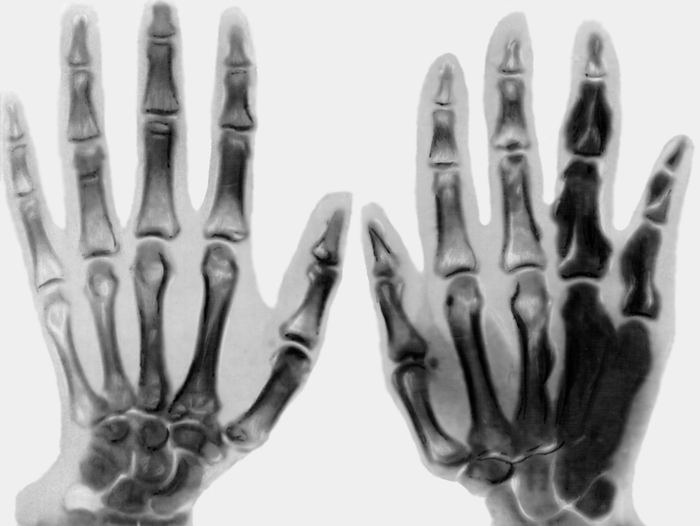

Для более точной диагностики врач может рекомендовать рентгеновское исследование здоровой кисти. Это позволит сравнить состояние костей и суставов, выявить возможные отклонения и назначить соответствующее лечение.

По завершении обследования специалист по рентгенологии интерпретирует полученные изображения. В этом процессе анализируются состояние костей и суставов, их взаимное расположение, а также структура и плотность костной ткани.

Здоровье костей определяется их однородной структурой. На рентгеновских снимках не должно быть затемнений на светлых участках, а суставная щель должна быть четко видна.

Рентген кистей норма?

В норме кости кистей рук должны иметь однородную структуру. На снимках не должно быть затемнений на белых участках. Между костями должна присутствовать щель. Если повреждению подверглась только одна кисть, для более точного диагностирования патологии могут сделать рентген и здоровой конечности.